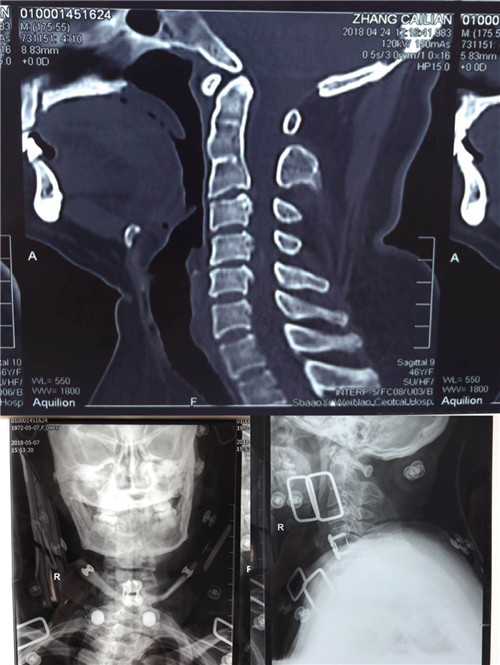

入院后,骨一科医师对患者做进一步检查。颈椎CT显示,颈5/6椎间盘突出,颈3/4、4/5、6/7椎间盘突出;颈椎MR显示,颈4/5、6/7椎间盘突出,颈5/6椎间盘突出并椎管狭窄。

术前